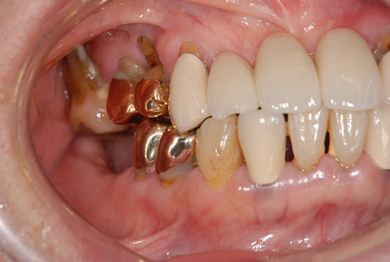

インプラントの症例写真 IMPLANT

| 性別/年齢 | 女性 / 58歳 | ||||||||||||||||||||||||||||||||

| 主訴 | インプラント治療を希望。 | ||||||||||||||||||||||||||||||||

| 治療内容 | インプラント8本(抜歯即日スピードインプラント、サイナスリフト)、ハイブリッドセラミック8本 | ||||||||||||||||||||||||||||||||

| 総治療費 | 3,495,050円 | ||||||||||||||||||||||||||||||||

| 治療期間 | 1年0ヶ月 |